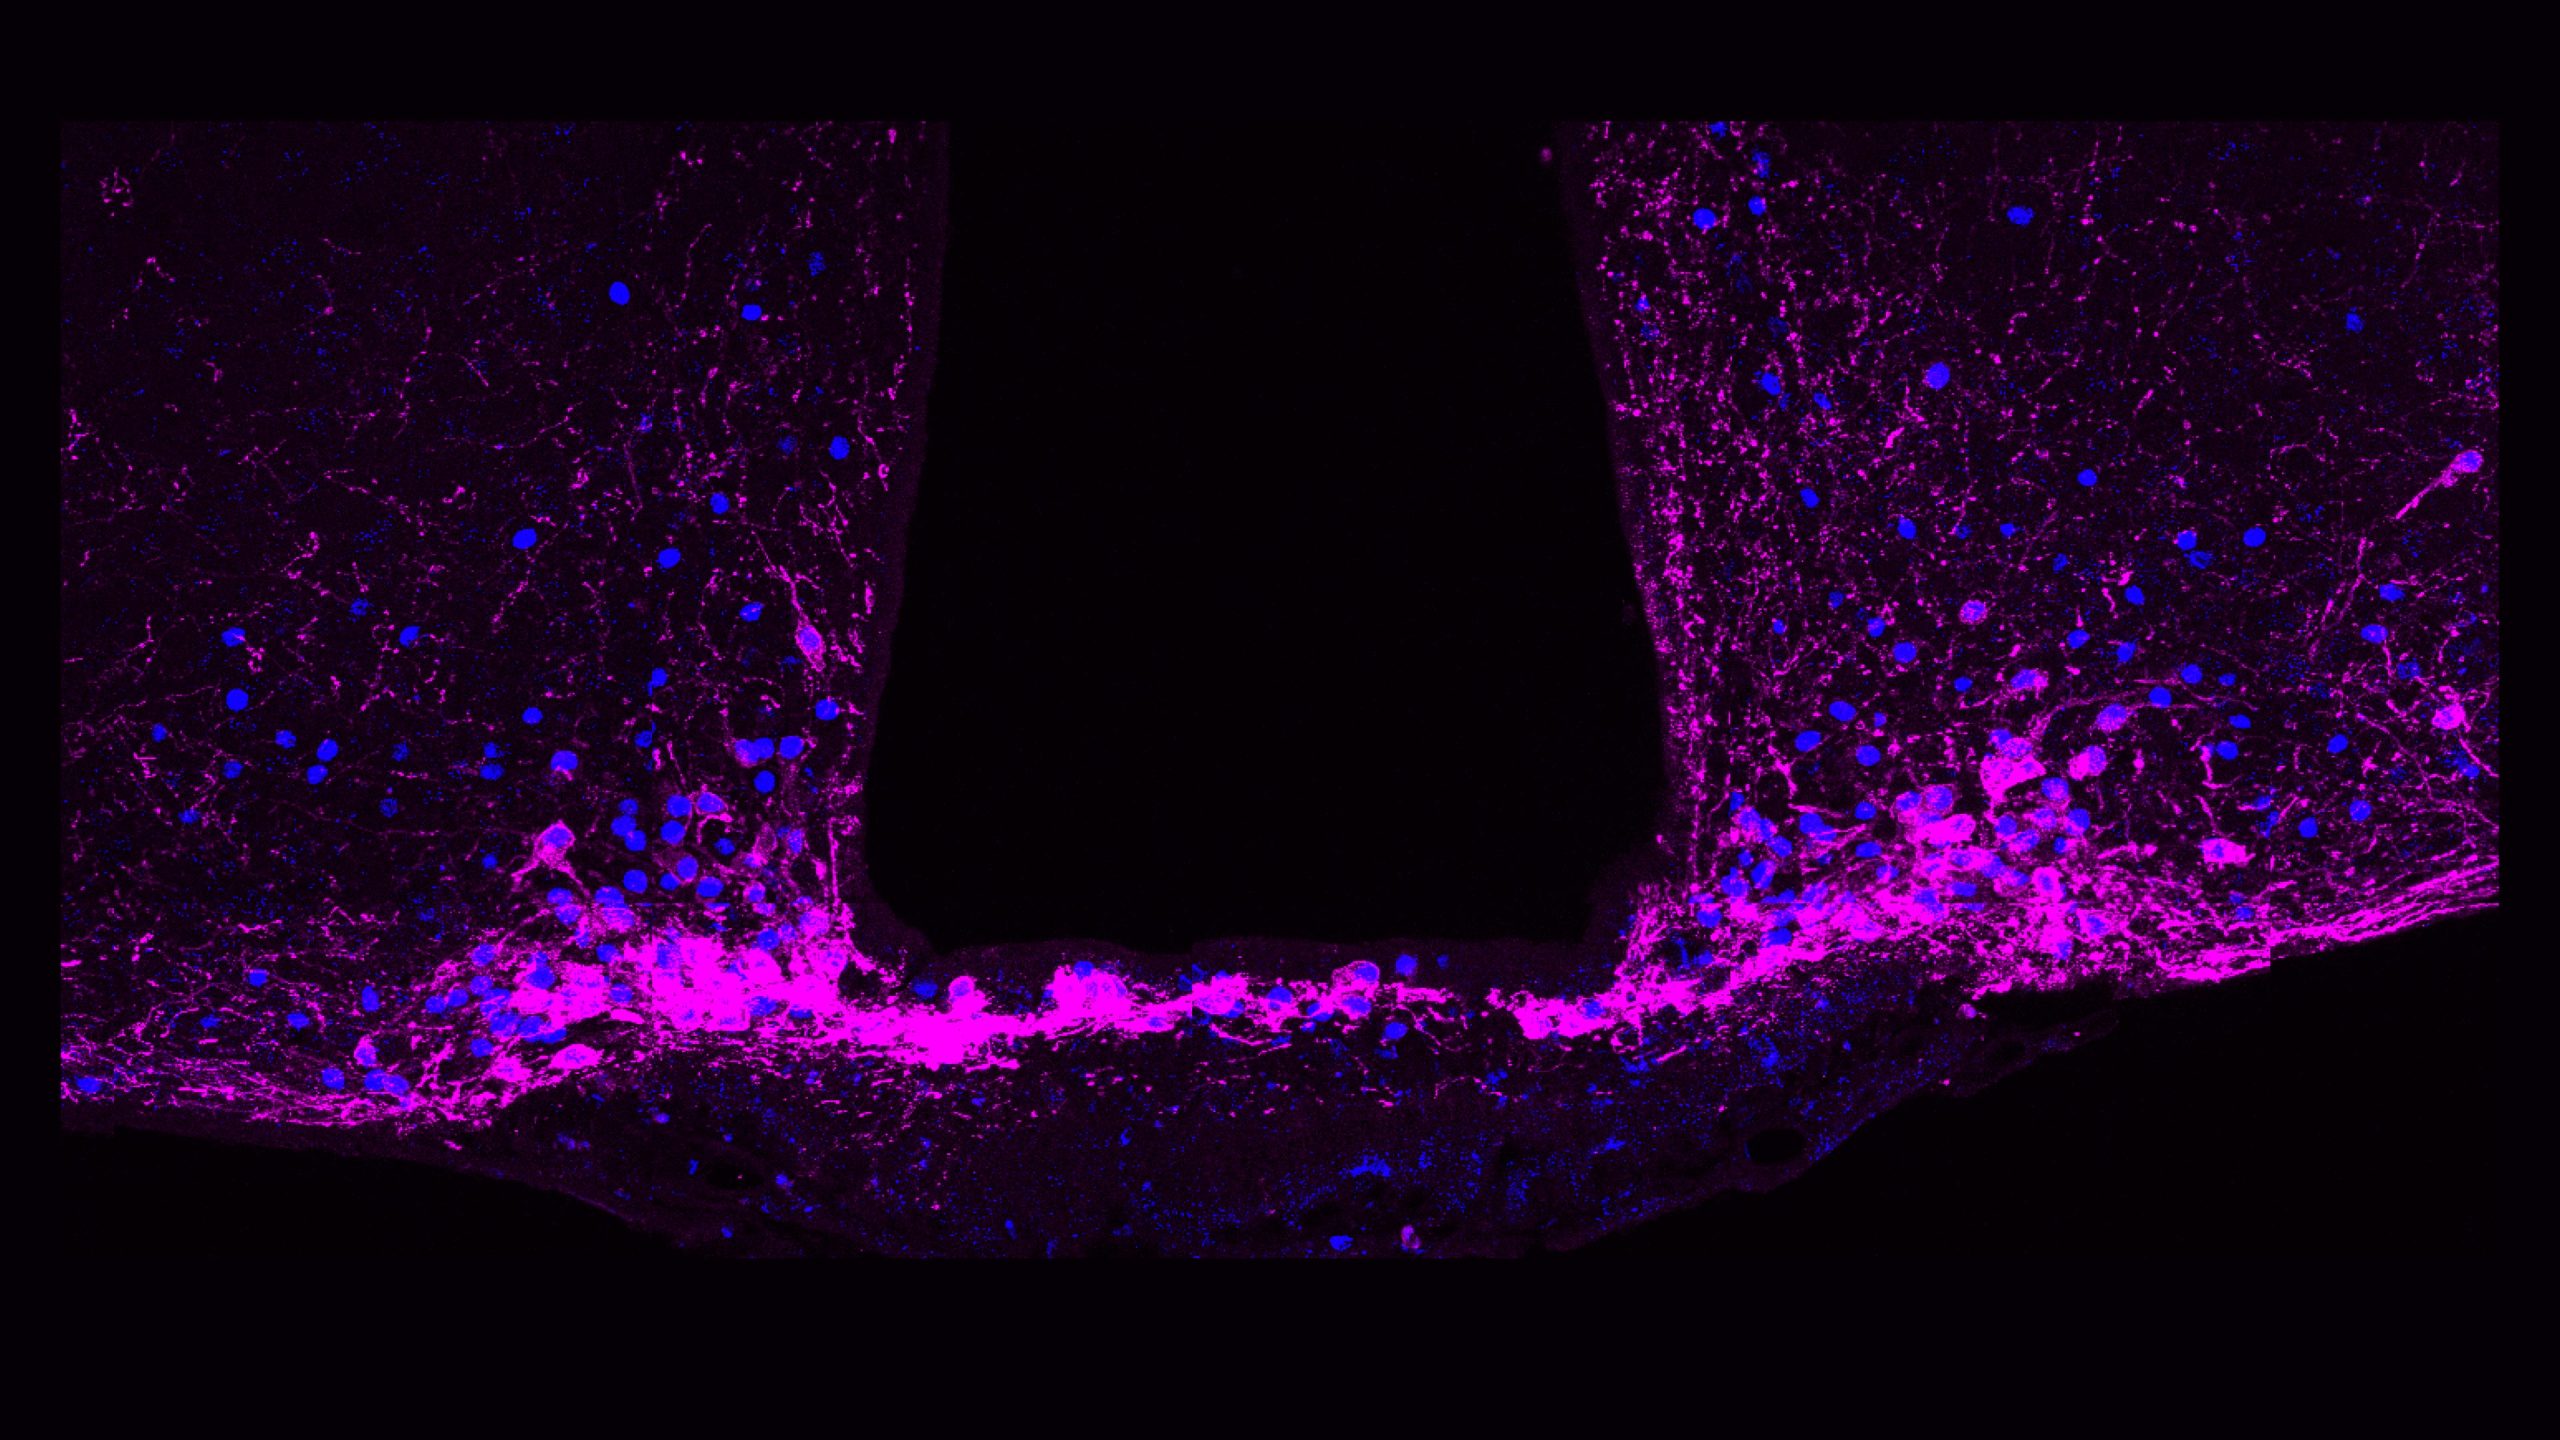

In un nuovo studio, Betley e ricercatori dell’Università di Pittsburgh e dello Scripps Research Institute hanno identificato un insieme di cellule cerebrali che svolgono un ruolo centrale nel controllo del dolore cronico. Queste cellule, note come neuroni che esprimono il recettore Y1 (Y1R), si trovano in una parte del tronco encefalico chiamata nucleo parabrachiale laterale (lPBN). Si attivano in stati di dolore di lunga durata, ma elaborano anche altri segnali legati alla fame, alla paura e alla sete. Questa sovrapposizione suggerisce che il cervello può adattare le risposte al dolore quando altre esigenze di sopravvivenza sono più urgenti.

Nell’ambito di una collaborazione con il laboratorio Taylor di Pitt, i ricercatori hanno utilizzato l’imaging del calcio per osservare i neuroni attivarsi in tempo reale in modelli preclinici di dolore acuto e cronico. Hanno scoperto che i neuroni Y1R non si limitavano a una breve attivazione in risposta al dolore acuto, ma continuavano a attivarsi in modo costante anche durante il dolore persistente, un fenomeno che i neuroscienziati chiamano “attività tonica”.

I ricercatori hanno anche caratterizzato l’identità molecolare e anatomica dei neuroni Y1R nel lPBN. Hanno scoperto che i neuroni Y1R non formavano due popolazioni anatomiche o molecolari ordinate. Questi neuroni erano invece distribuiti in molti altri tipi cellulari.

“È come guardare le auto in un parcheggio“, afferma Betley. “Ci aspettavamo che tutti i neuroni Y1R fossero un gruppo di auto gialle parcheggiate insieme, ma qui i neuroni Y1R sono come vernice gialla distribuita su auto rosse, auto blu e auto verdi. Non sappiamo esattamente perché, ma pensiamo che questa distribuzione a mosaico possa consentire al cervello di smorzare diversi tipi di input dolorosi su più circuiti”.